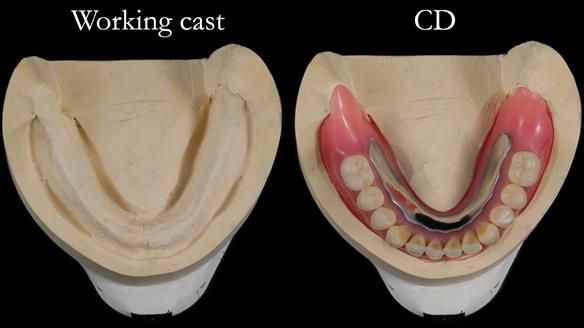

The detailed clinical situation and treatment process are outlined below, with clinical work provided by me and technical work by Rowan Garstang. The treatment spanned 12 months, involving removing 5 upper anterior teeth, adding to an existing upper RPD, followed by creating and fitting metal based complete dentures.